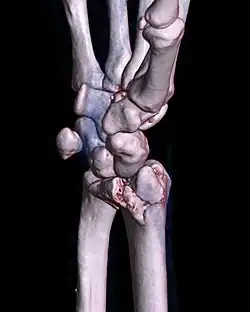

| A palmar Barton's fracture of the right wrist, as shown on a 3D-rendered CT scan | |

A Barton's fracture is a type of wrist injury where there is a broken bone associated with a dislocated bone in the wrist, typically occurring after falling on top of a bent wrist.[1] It is an intra-articular fracture of the distal radius with dislocation of the radiocarpal joint.[2]